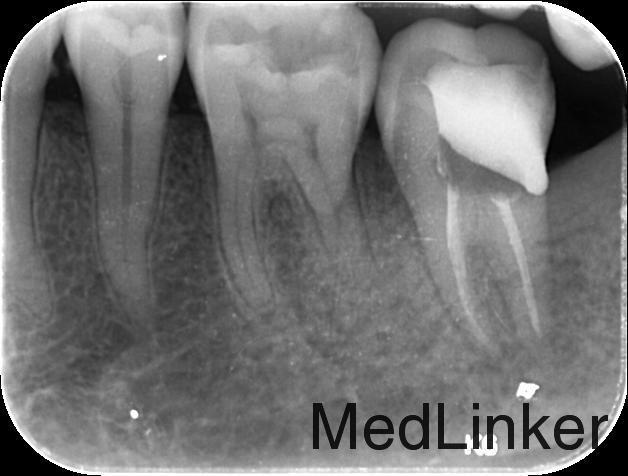

诊断:1、38近中阻生 2、37慢性牙髓炎 治疗计划:1、拔除38阻生齿 2、37根管治疗后冠修复 治疗:1. 37利多卡因局麻下,去腐未净露髓,暴露髓腔,降牙合,探及MB、ML、D三个根管口,置非砷慢失活剂,氧化锌水门汀暂封。嘱勿用患牙咬物。 38利多卡因局麻下分龈,去除近中阻力,挺松,拔除,搔刮牙槽窝,复位,局部压迫止血。 2.主诉:左下后牙上次治疗后无不适。 检查:37暂封物在,叩痛(—),牙体无松动,牙龈无明显红肿。 处置:37去除暂封物,拔残髓,10号C锉疏通根管,干燥根管,电测工作长度WL:MB=ML=18mm,D=18.5mm。EDTA下,常规预备至35#,3%过氧化氢和生理盐水冲洗+超声荡洗根管交替进行。隔湿,干燥根管,封CP棉球, 氧化锌水门汀暂封。嘱勿用患牙咬物。 3.主诉:左下后牙上次治疗后无不适。 检查:37暂封物在,叩痛(—),牙体无松动,牙龈无明显红肿。 处置:37去除暂封物,取出棉球,生理盐水冲洗并干燥根管,复测工作长度同前:MB=ML=18mm,D=18.5mm。进口根充糊剂+牙胶尖冷侧压根管充填,氧化锌水门汀暂封,术后拍片示:37根充恰填。嘱勿用患牙咬物。 建议:37桩冠修复